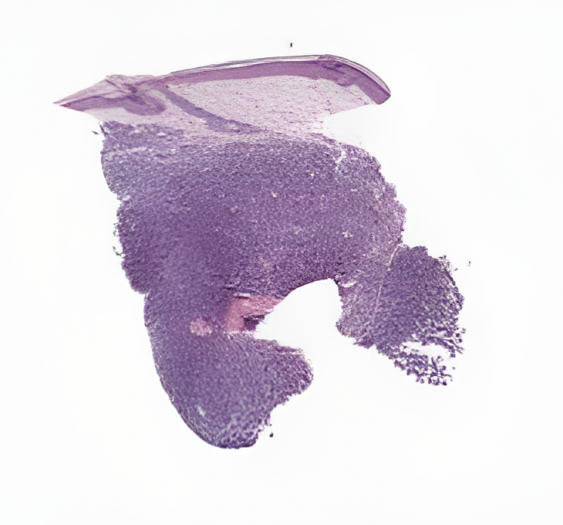

病理学数字切片

炎症